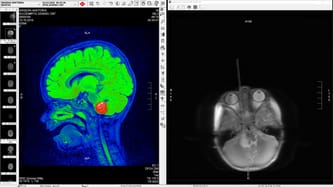

23.03.2022 r. odbyła się wielogodzinna operacja, niestety guza nie udało się usunąć w całości ponieważ wyrasta z pnia mózgu. Usunięte zostało około 80 %.

Po wielu tygodniach oczekiwań dostaliśmy wynik histopatologii: glejak grade II, był to dla nas kolejny cios. Postanowiliśmy zweryfikować wynik prywatnie poza granicami naszego kraju. Wynik z kliniki w Bonn okazał się być bardziej optymistyczny, guz okazał się być glejakiem grade I, co oznacza dla nas szanse na wyleczenie córki, które możliwe byłoby w przypadku usunięcia całego guza.

Mimo że ostatnia badania pokazały, że jest to wolno rosnący guz, rezonans z 14.06.2023 r. pokazał duży wzrost guza, który musi być jak najszybciej ponownie usunięty, by nie zagrażał zdrowiu i życiu Wiktorii.

Nasza córeczka znów staję oko w oko ze śmiercią i znów musi przejść skomplikowaną operację, by mogła dalej żyć! Wiemy tylko jedno – musimy być gotowi w każdej chwili podjąć walkę o nasze dziecko! Guz jest już bardzo duży – zagraża zdrowi i życiu naszej córeczki.